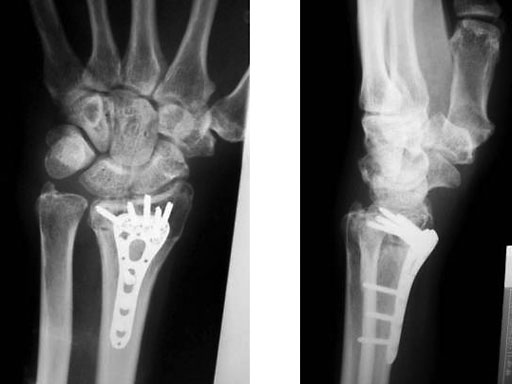

Fig 3a-b Post-op 3 months